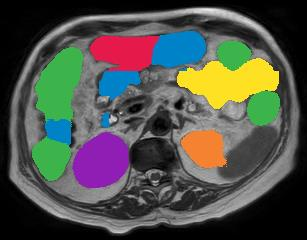

Vision transformers, with their ability to more efficiently model long-range context, have demonstrated impressive accuracy gains in several computer vision and medical image analysis tasks including segmentation. However, such methods need large labeled datasets for training, which is hard to obtain for medical image analysis. Self-supervised learning (SSL) has demonstrated success in medical image segmentation using convolutional networks. In this work, we developed a \underline{s}elf-distillation learning with \underline{m}asked \underline{i}mage modeling method to perform SSL for vision \underline{t}ransformers (SMIT) applied to 3D multi-organ segmentation from CT and MRI. Our contribution is a dense pixel-wise regression within masked patches called masked image prediction, which we combined with masked patch token distillation as pretext task to pre-train vision transformers. We show our approach is more accurate and requires fewer fine tuning datasets than other pretext tasks. Unlike prior medical image methods, which typically used image sets arising from disease sites and imaging modalities corresponding to the target tasks, we used 3,643 CT scans (602,708 images) arising from head and neck, lung, and kidney cancers as well as COVID-19 for pre-training and applied it to abdominal organs segmentation from MRI pancreatic cancer patients as well as publicly available 13 different abdominal organs segmentation from CT. Our method showed clear accuracy improvement (average DSC of 0.875 from MRI and 0.878 from CT) with reduced requirement for fine-tuning datasets over commonly used pretext tasks. Extensive comparisons against multiple current SSL methods were done. Code will be made available upon acceptance for publication.